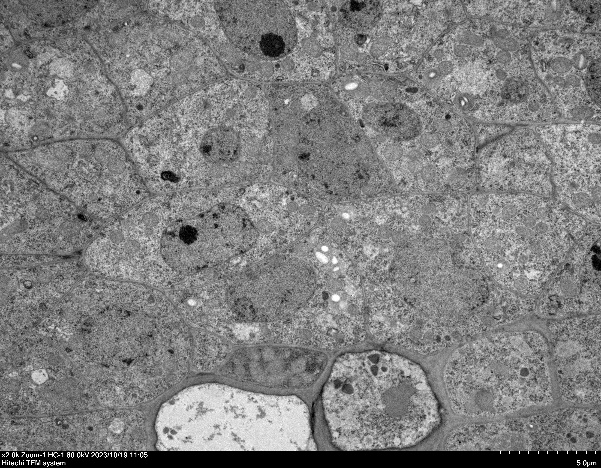

组织超微结构研究:线粒体、内质网、突触等亚细胞器形态观察

病理机制研究:炎症、损伤模型中细胞器改变观察